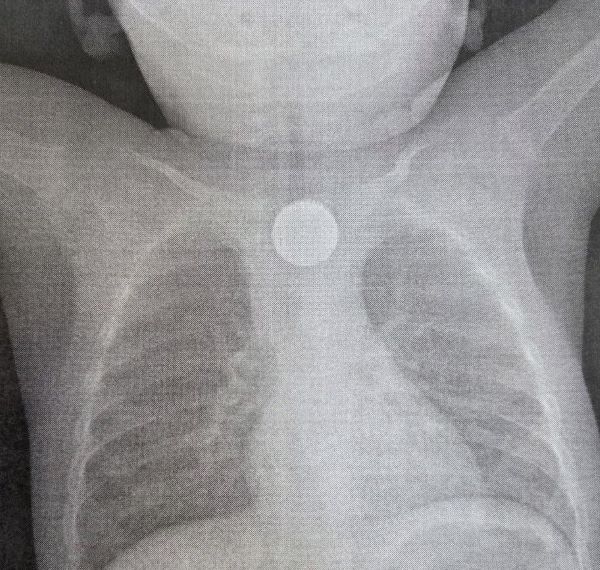

27 ноября в приёмно-диагностическое отделение Детской республиканской клинической больницы (ДРКБ) поступил годовалый малыш.

Как оказалось, ребёнка рвало, затем его состояние усугубилось повышением температуры тела и появлением хрипов при дыхании. Родители сначала обратились за медицинской помощью в центральную районную больницу, где врачи обнаружили в пищеводе инородное тело. После ребёнок был сразу направлен в ДРКБ.

Бригада медиков детской больницы оперативно удалила из пищевода инородные тела. Во время эндоскопического вмешательства были извлечены 2-рублевая монета и дисковая литиевая батарейка. Литиевая батарейка, находясь в пищеводе, вызвала химический ожог слизистой оболочки 3 степени, представляющий серьёзную угрозу для жизни ребёнка.